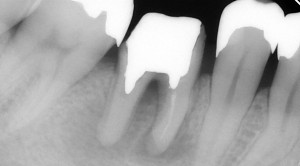

歯根端切除術後です。

根の先端が短くなっているのが分かると思います。

わずか(およそ3ミリ)ですが、骨から根の先端が出ています。たったこれだけが骨の中に納まっていないだけで治らないのです。

根の先端を3ミリほど切った状態です。この後しばらくして症状は全くなくなりました。